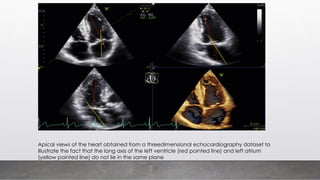

Apical views of the heart obtained from a threedimensional echocardiography dataset to

illustrate the fact that the long axis of the left ventricle (red pointed line) and left atrium

(yellow pointed line) do not lie in the same plane